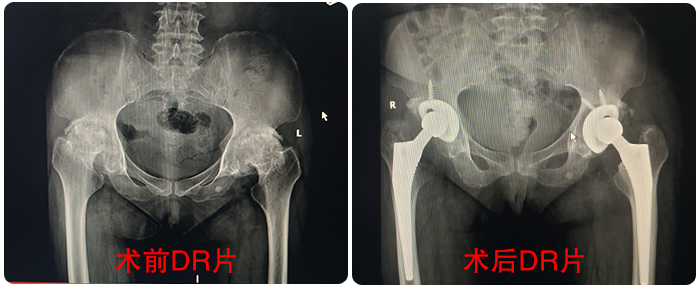

童奶奶術(shù)前術(shù)後對(duì)比影(yǐng)像